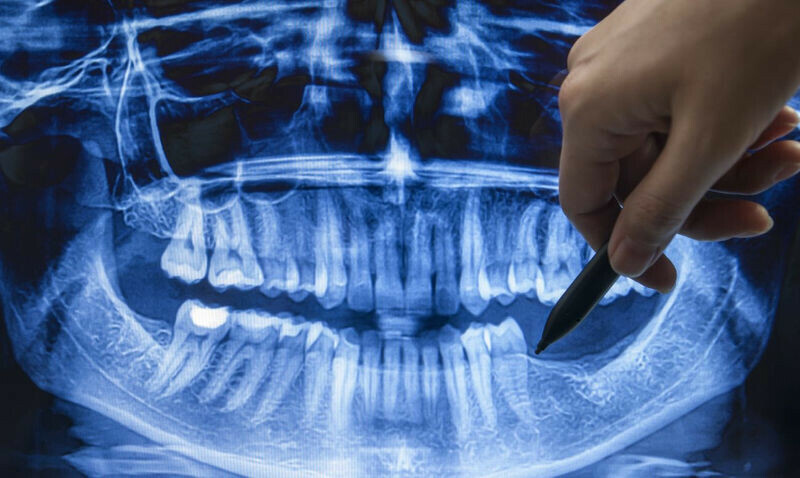

Ученые научились выращивать новые зубы

Фото: РИА Новости Японские ученые с сентября начнут исследования по выращиванию новых зубов у людей.

Пока речь идет о пациентах с врожденной олигодонтией - отсутствием шести или более зубов.

«У пациентов с аплазией зубов в период развития челюстной кости в юном возрасте наблюдается отсутствие зубов, что делает сложным использование зубных протезов и имплантатов. В период роста наблюдается снижение функции жевания, что негативно сказывается на развитии и может привести к атрофии костей, поддерживающих зубы», - поясняют эксперты Медицинского исследовательского института при Больнице Китано в Осаке.

На помощь пришли мыши: у некоторых с генетическим дефектом белка USAG-1 формируются избыточные зубы, при этом «скрещивание мышей с аплазией зубов и мышей с избыточными зубами с дефектом гена USAG-1 приводит к восстановлению формирования зубов». Местное введение нуклеиновой кислоты USAG-1siRNA мышам с аплазией зубов позволяет восстановить отсутствующие зубы. Этот же способ испытали на собаках породы бигль, которые наравне с мышами имеют высокую степень аминокислотного сходства белка USAG-1 с человеком.

Теперь дошли руки и до человека - для этого к осени отберут «мужчин без видимых проблем со здоровьем в возрасте от 30 до 65 лет, у которых отсутствует один или более моляров». Продлятся исследования до августа 2025 года, сообщает РИА Новости.